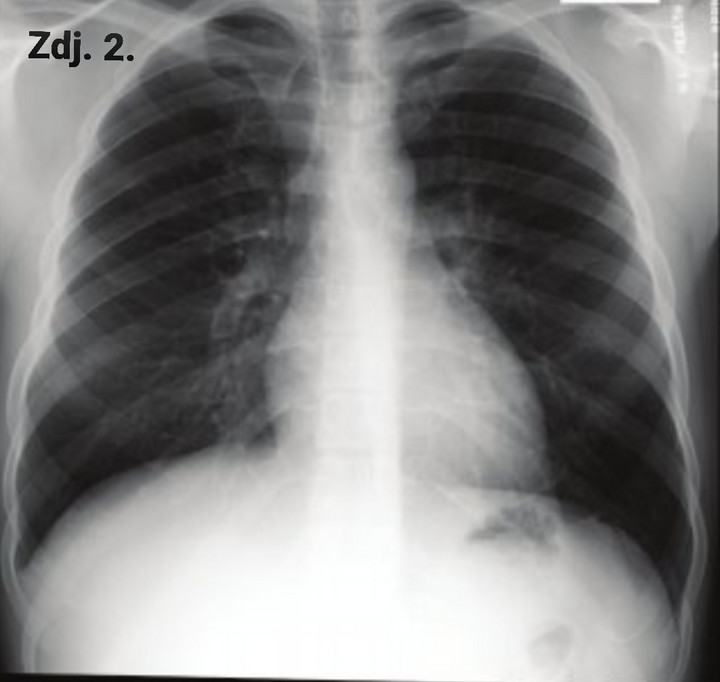

Na zdjęciu nr 3 a i b widzimy przekrój przez klatkę piersiową, uzyskany za pomocą tej metody obrazowania. Zdjęcia pokazują zakres zmian śródmiąższowych, czyli te wszystkie białe jakby rozlane plamy u jednego pacjenta. Oceniamy je na różnych wysokościach płuc, tutaj na zdjęciu 3a na wysokości szczytów płuc (tuż poniżej ramion) i na poziomie serca (zdj. 3b). Procentowa zawartość zdrowego (czarnego) miąższu jest niewielka. Oczywiście w większości przypadków zmiany w toku leczenia zmniejszają się, a obraz płuc ulega uporządkowaniu, ale ten proces wymaga czasu. Ile? Na tą chwilę, nie mamy jeszcze długoterminowych, opartych na dużej liczbie przypadków badań, które pokazałyby, jak długo i w jakim stopniu organizm będzie wracał do pierwotnego stanu i czy w ogóle wróci.

Zdjęcie 3a

Zdjęcie 3b